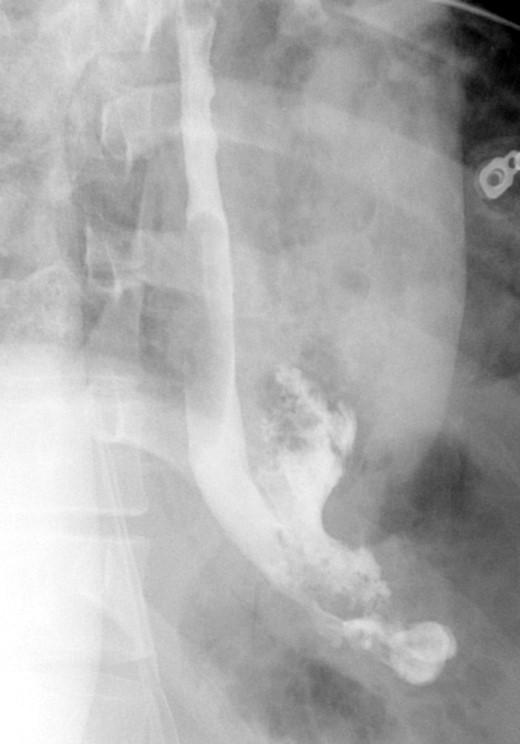

A follow-up EGD was performed 6-weeks later for stent removal. Although the stent had migrated slightly, it continued to cover the previous perforation site. The stent was removed, and the esophagus appeared well healed with no residual tear. Contrast study showed no residual leak or significant stricture (Fig. 4). On follow-up endoscopy, biopsies from the proximal and distal esophagus revealed 20 eos/hpf and 30 eos/hpf, respectively. The patient was kept on PPI and started on topical steroids and continued to do well with no reported symptoms on the last follow up 9 months and two years and a half after the initial presentation.

Shows interval removal of the esophageal stent with no evidence of an esophageal leak.